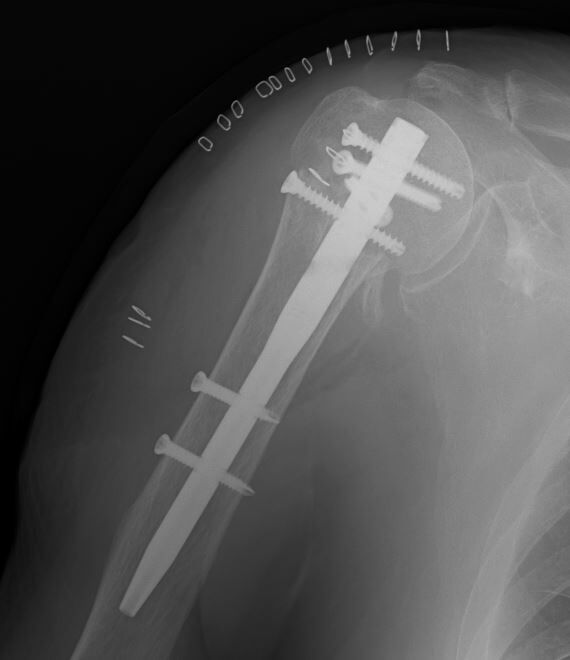

先日、上腕骨近位端骨折の骨折観血的手術を行いました。4-part骨折でしたが、なんとかカタチになってホッとしています。